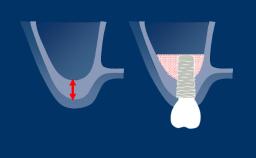

The scientifically documented success of implants has led to the development of many different implant designs, materials, surface technologies, and surgical methods.

Therefore, choosing an implant system requires careful consideration.

This Module will review the various factors that should influence the clinician's selection of the most appropriate system for their patients.